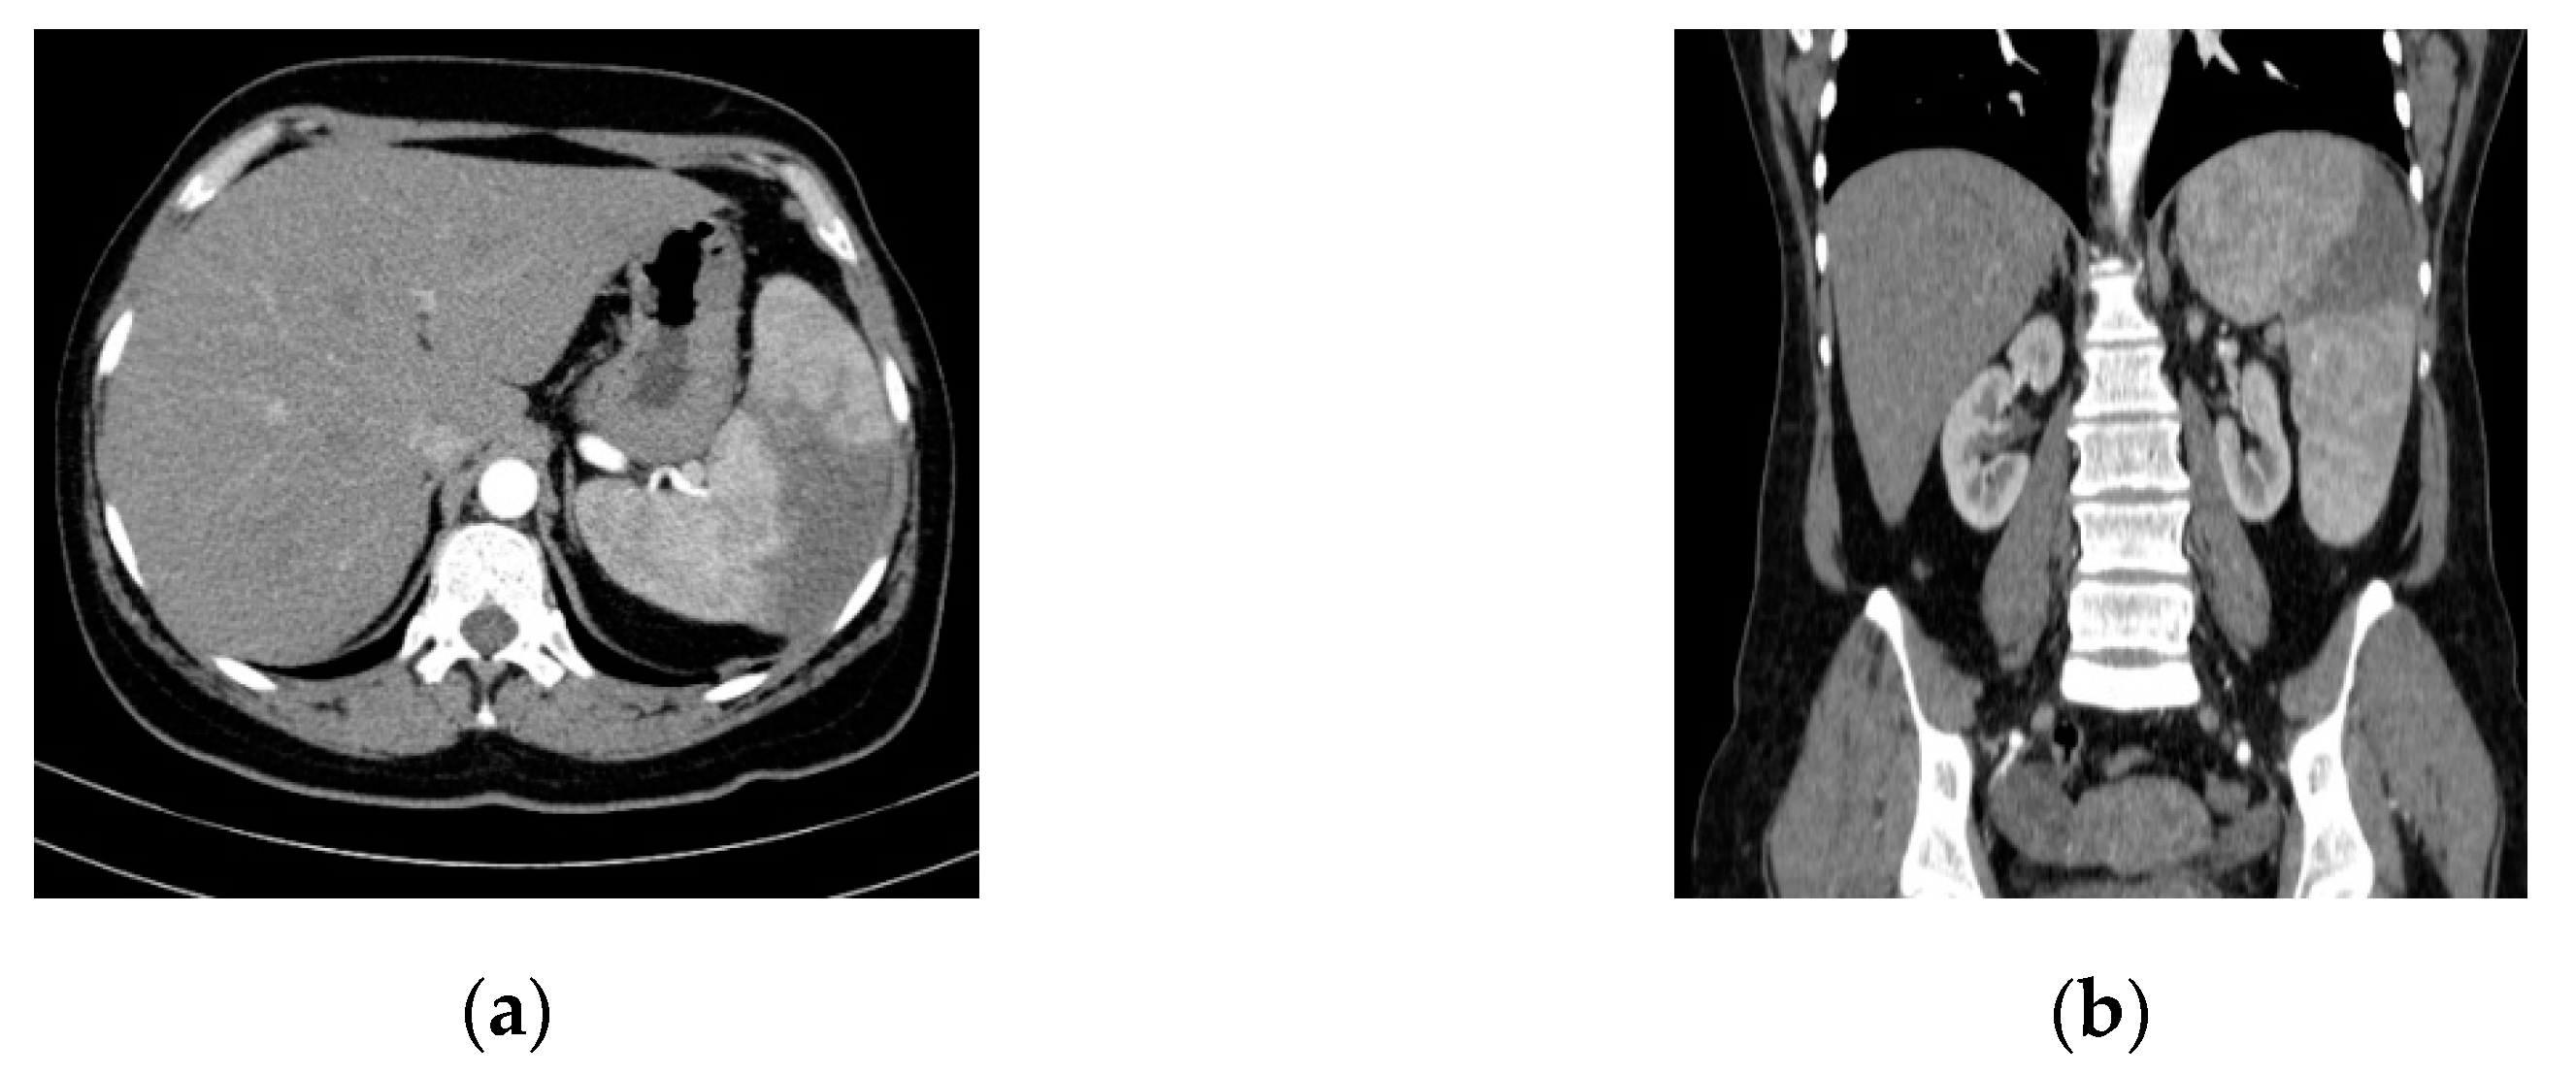

An abdominal ultrasound examination (HS60 ultrasound machine, Samsung Medison Co., Ltd., Seoul, Korea) and CT study (Somatom Emotion™ 16-slice, Siemens Healthcare GmbH, Erlangen, Germany) highlighted splenomegaly and splenic infarction (Figure 1).

Figure 1.

Abdominal/pelvic contrast-enhanced CT scan (Optiray™ 350). Splenomegaly and splenic infarction are depicted in (a) axial and (b) coronal sections.

Intra-abdominal embolic complications are relatively common in cases of left-sided infective endocarditis. The spleen and the brain are the most frequent sites of systemic embolism [27]. Jasarevic et al. reviewing abdominal angiographic CT studies, suggested that splenic infarction may be suspected in the presence of a consistently triangular-shaped area with hypodensity on portal venous phase images, with no late enhancement [28]. In our case, SI was suspected due to the presence of intense and prolonged pain in the splenic lodge as well as abdominal ultrasonography and was confirmed by abdominal CT scan. No extra-splenic embolic lesions (kidney, liver) related to IE were detected.